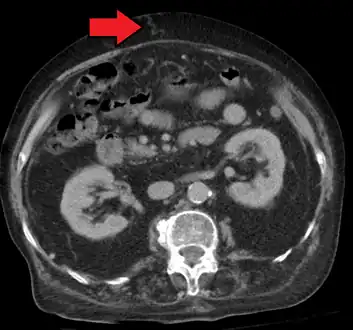

-

Magnetic resonance imaging of portal hypertension -

Portal hypertension due to cirrhosis resulting in revascularization of the umbilical vein

Ultrasonography (US) is the first-line imaging technique for the diagnosis and follow-up of portal hypertension because it is non-invasive, low-cost and can be performed on-site.[12]

A dilated portal vein (diameter of greater than 13 or 15 mm) is a sign of portal hypertension, with a sensitivity estimated at 12.5% or 40%.[13] On Doppler ultrasonography, a slow velocity of <16 cm/s in addition to dilatation in the main portal vein are diagnostic of portal hypertension.[14] Other signs of portal hypertension on ultrasound include a portal flow mean velocity of less than 12 cm/s, porto–systemic collateral veins (patent paraumbilical vein, spleno–renal collaterals and dilated left and short gastric veins), splenomegaly and signs of cirrhosis (including nodularity of the liver surface).[12]

The hepatic venous pressure gradient (HVPG) measurement has been accepted as the gold standard for assessing the severity of portal hypertension. Portal hypertension is defined as HVPG greater than or equal to 5 mm Hg and is considered to be clinically significant when HVPG exceeds 10 to 12 mm Hg.[15]